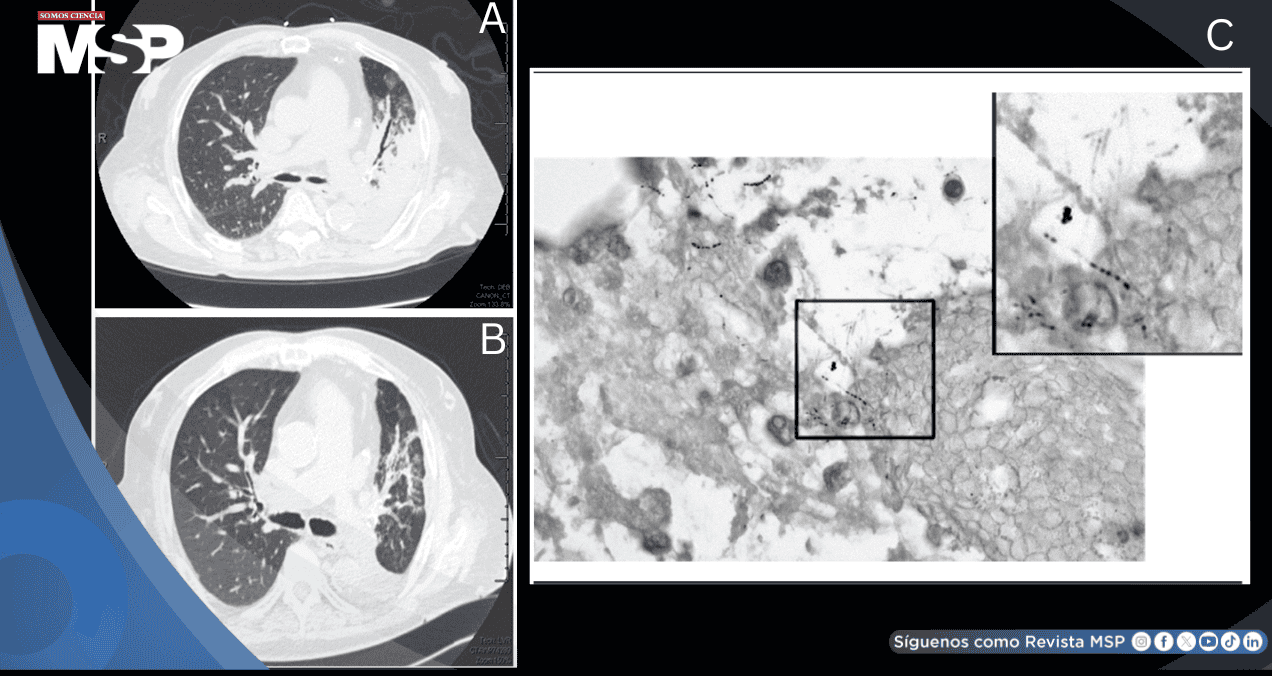

El caso ilustra cómo el uso prolongado de corticosteroides inhalados y la disfunción inmunológica asociada a EPOC pueden predisponer a infecciones atípicas, requiriendo un alto índice de sospecha diagnóstica y técnicas invasivas para su identificación.